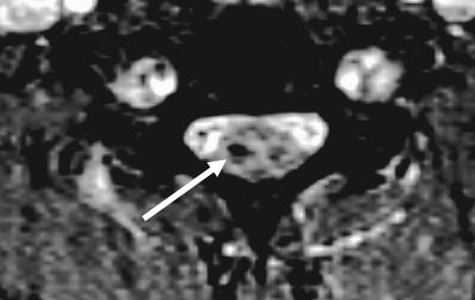

КТ. Перелом тела С2 (красные стрелки).

Особую категорию составляют пациенты, у которых, несмотря на наличие неврологической симптоматики, не выявляется изменений при рентгенографии или КТ. Число таких пациентов составляет около 10%. Среди различных механизмов подобных травм наиболее вероятна кратковременная компрессия спинного мозга задней продольной связкой и дисками, либо, жёлтой связкой и пластиной дуги. Посколько резкие сгибания и разгибания наблюдаются при высокой подвижности в сегментах, такие травмы более вероятны в шейном отделе позвоночника. Спондилолиз усугубляет эту ситуацию, приводя к центральному синдрому спинного мозга. В этих случаях необходимой является МРТ позвоночника. Характерными находками, которые мы часто видим при травмах при МРТ в СПб, являются отёк спинного мозга и гематома, причём последняя при МРТ позвоночника плохим прогностическим фактором в отношении восстановления неврологического дефицита. К наиболее тяжелым осложнениям шейной травмы относится расслоение магистральных артерий, определяемое по МРТ, МРА или КТ и КТА. В высоком поле такой вид травм лучше виден чем в открытом МРТ. МРТ СПб позволяет выбирать место МРТ, однако, острая травма шейного отдела позвоночника требует высокоспециализированного нейрохирургического отделения

МРТ шейного отдела позвоночника. Острая травма. Компрессия спинного мозга, отек и контузия. Сагиттальная Т2-взвешенная МРТ.

МРТ шейного отдела позвоночника. Аксиальная Т2-взвешенная МРТ. Кровоизлияние в спинной мозг.